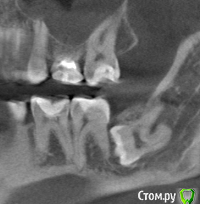

Подскажите пожалуйста, как правильно поступить с моими 8-ками?

Их, действительно, надо срочно удалять? Мне 28 лет. Какова вероятность, что они меня вообще не побеспокоют?

Какие существуют риски их удалять и какие риски их не удалять ?

post-51158-0-93444800-1490961203_thumb.png